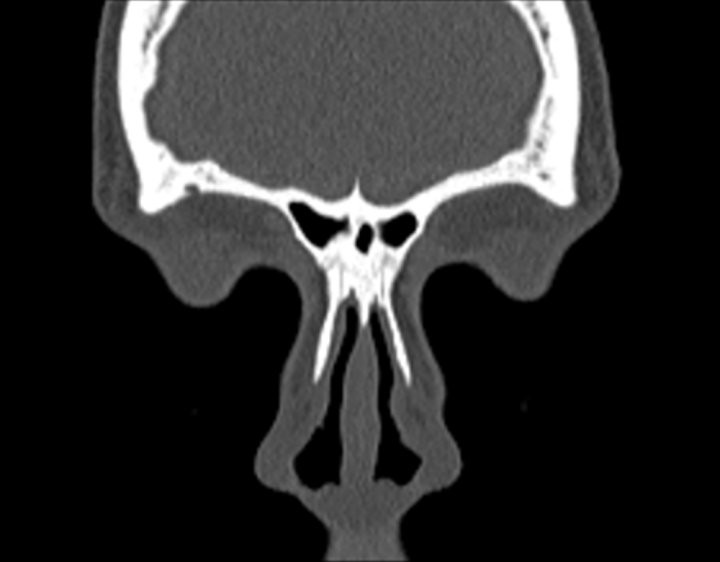

Click any image for labels.